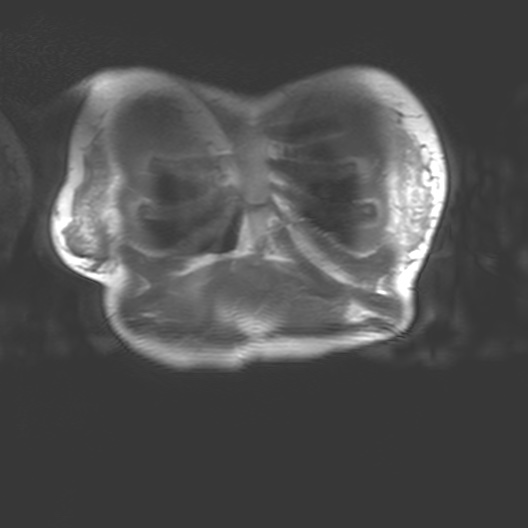

Corporeal matter as perceived by MRI straddles definitions of substance, organism, subject and object. MRI interacts with the body through nuclear magnetic resonance and electrodynamics, bringing us into contact with the body as a person, as an assemblage of biochemical reactions, as a patient and a cellular, molecular, atomic and subatomically composed entity.

MRI is a non-invasive biomedical imaging technology that visualises tissues within the body. MRI is an interesting piece of physics that interacts with the body. As a technology it draws on the quantume mechanical properties embedded in corporeal matter - particularly hydrogen ions, also known as protons (H+). MRI brings together multiple aspects of our ontology. MRI interacts with the body through nuclear magnetic resonance and classical electrodynamics and thus physics allows us to connect to the abject. This brings us into contact with the body as a person, a patient, a member of a community, and as a cellular, molecular, atomic and subatomically composed entity.

I began my investigation by taking part in MRI trials at the Cancer Centre in 2018 with Dr Heather Fitzke. MRI images confront us with the fact that our bodily materiality acts beyond us and that medical technology shapes our sense of self.

Seeing my organs autonomously pulsing on the monitor in the control room had a pronounced impact on me. It was like looking into a rockpool within my own body. The affecting power of MRI (its power to change our emotions) is in its potential to reveal autonomic bodily functions and diseases which are beyond our control. The data on the screen revealed my autonomous self: peristalsis, bowel movements, digestion, heartbeats and respiration. Through MRI, anatomy is seen as embedded and relational.

I felt a deep sense of fascination with how my organs moved and worked. Haraway’s situated biopolitics argues for an account of the body as an environment, in a state of simultaneous dissolution and formation which I notice in my data. My organs seemed like invertebrates in a rockpool: a squishy pulsing ecosystem. Organs do not operate in isolation but are interconnected. Their autonomous pulsing and motion seemed creaturely and strange in contrast to my numerous encounters with preserved cadavers in the dissecting room. My organs keep me alive yet I have no conscious sense of their functioning. They function beyond me.